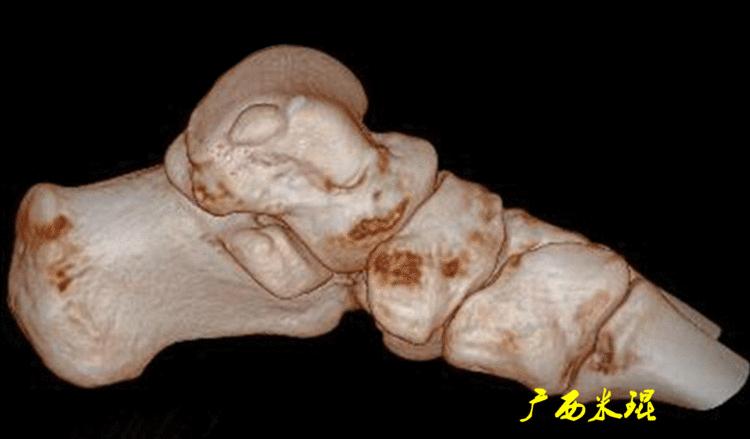

(2)CT检查

CT检查相对于X线检查而言更细致,但没有MR敏感,如果仅仅是软骨的病损,CT也容易漏诊。

即使这样,CT检查能够进行三维成像,可以更加直观的显示软骨剥脱的具体情况,这可是其他检查无法实现的。